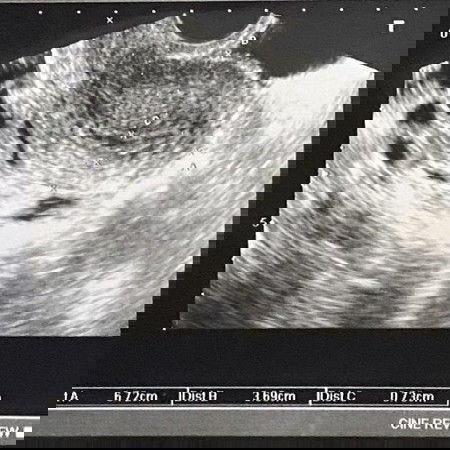

วันที่ 1 พ.ย.64 ตรวจพบว่าตัวเองตั้งครรภ์(ประจำเดือนขาด1เดือน) วันที่ 5 พ.ย 64 มีเลือดออกทางช่องคลอดและปวดท้องน้อยราวไปยันก้นกบ วันที่ 6 พ.ย 64 ไปหาหมอเพราะมีเลือดออกตอนท้องมันผิดปกติ หมอซาวด์ดูไม่เจอตัวเด็ก หมอตรวจเลือดพบว่าเป็นโลหิตจางและพาหะ(ให้ยามาทาน ) นัดมาตรวจใหม่ 9 พ.ย 64 วันที่ 9 พ.ย 64 ตรวจพบว่าชิ้นเนื้อไม่สามารถเจริญเติบโตไปเป็นเด็กได้ ต้องยุติการตั้งครรภ์ นัดผ่าตัดขูดหมดลูก 10 พ.ย 64 #ท้องแรกค่ะ